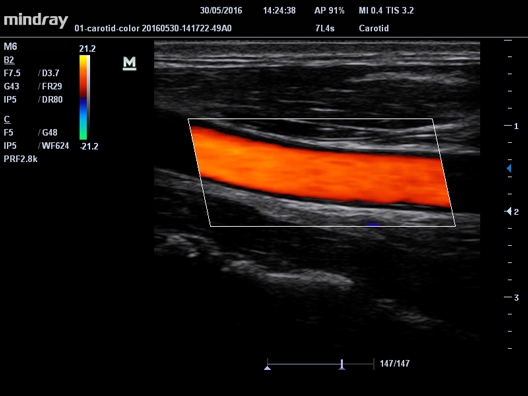

• Автоматический режим расчета комплекса интима-медиа. Определение толщины и сопоставление со стандартами.

• IMT Автоматический расчет толщины комплекса интима-медиа

• Vascular package для ангиологии, включая транскраниальные исследования